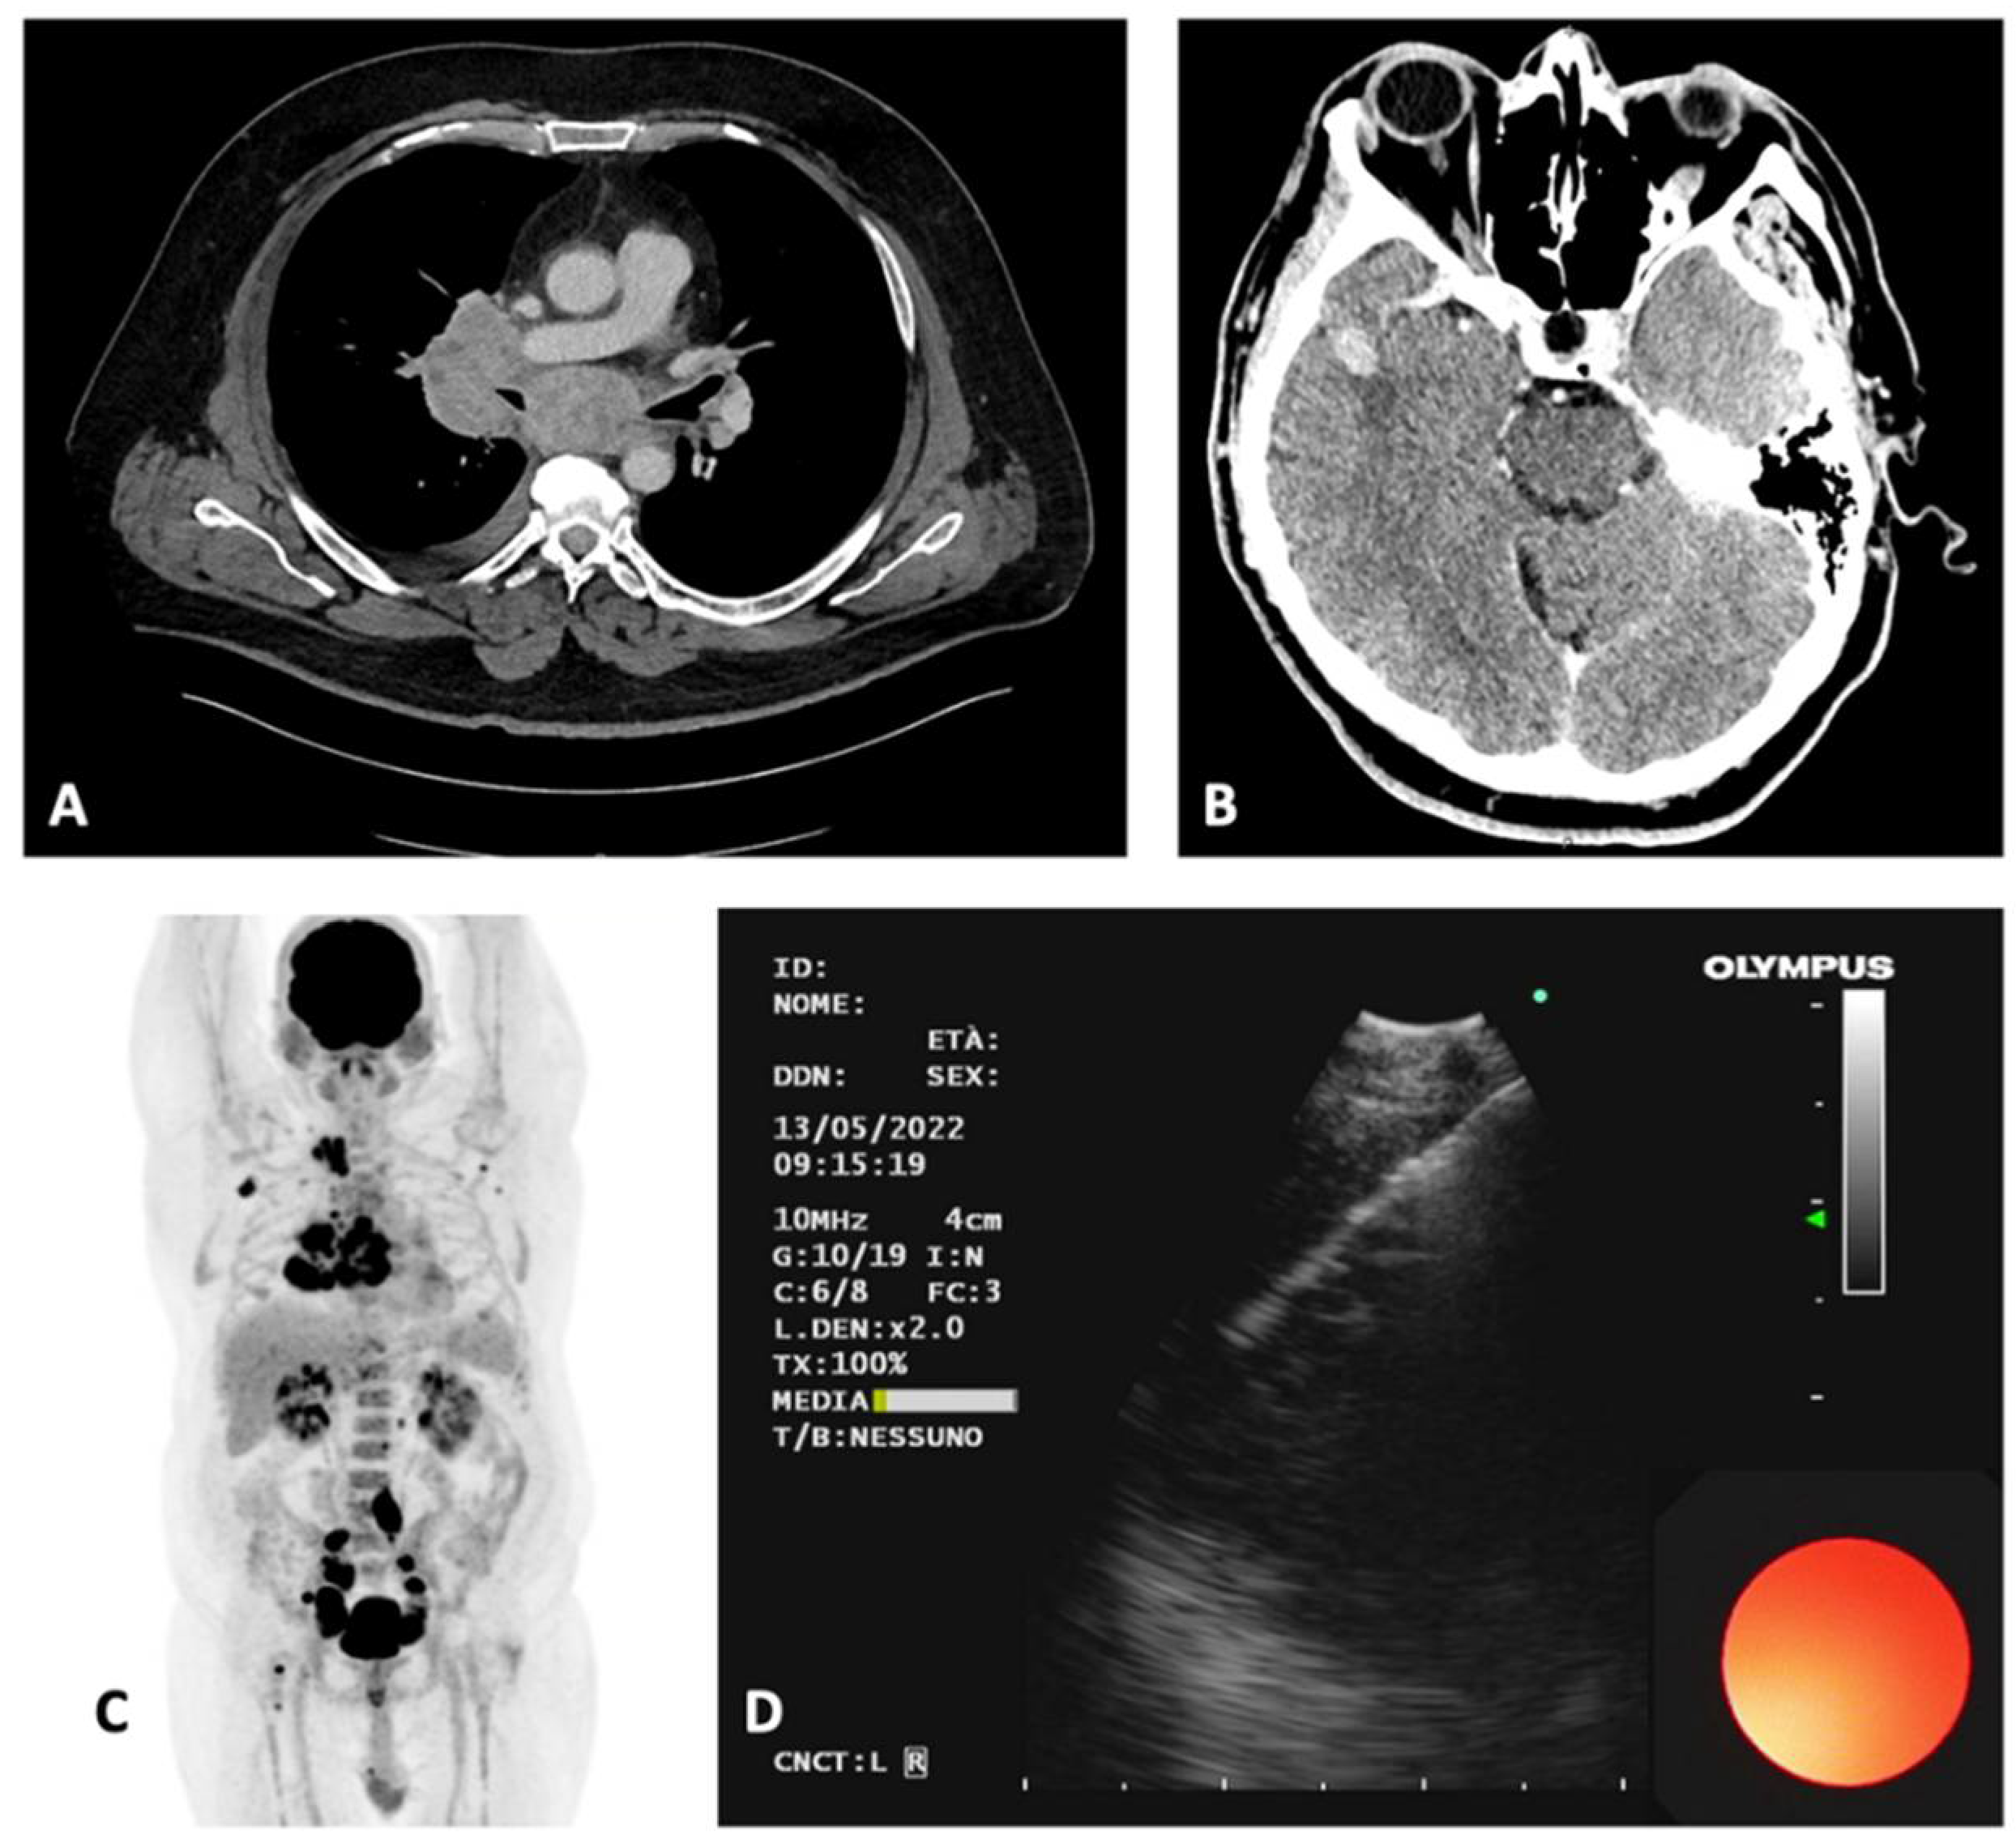

3.2. Case 2